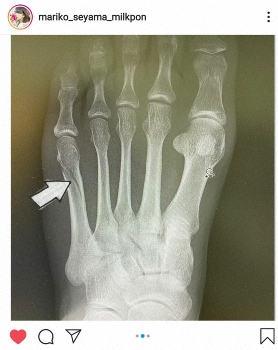

日本テレビの元アナウンサーでタレントの脊山麻理子(40)が13日にインスタグラムを更新し、人生で初めて骨折したことを明かした。

「人生初めての骨折をしました」「ひねったときに左第五中足を骨折していたようです」「初のギプス、初の松葉杖にゃ」として松葉づえ姿の写真とともに投稿。さらにレントゲン写真も2枚目に据えた。「すでに先週までに新作グラビアの撮影も終えておいて良かった!次の撮影予定は3月なので、それまでに治りますよおに」とつづった。ハッシュタグでは「踏み込まなければ痛くない 」「転んだときは痛かった 」「歩けることがどんなに素晴らしいことか気づけた」とした。